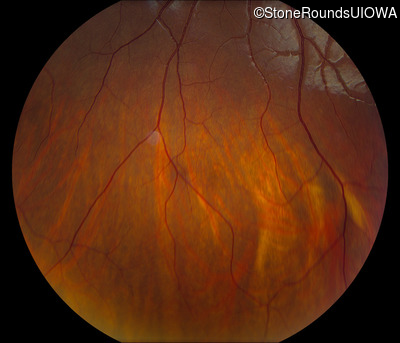

Visit at age: 16 years

Fundus Photography - Right - 10/125 -1

Exemplar